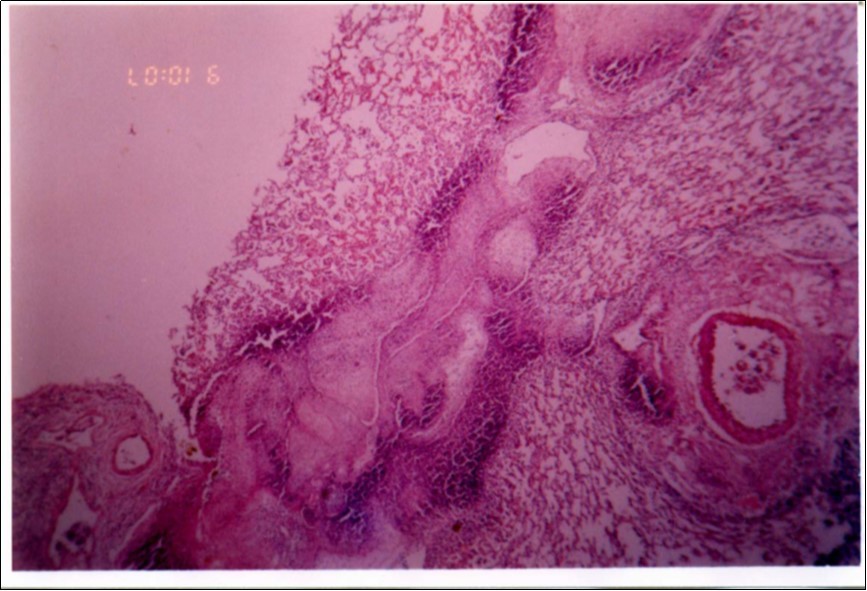

No mycoplasma was isolated from slaughterhouse samples. Three mycoplasma isolates were recovered from three out of six cases showing typical clinical signs and P.M. lesions. The isolates were identified as Mmm depending on cultural characteristics (Figure 1), digiton in test (Figure 2), and growth inhibition test.

Figure 1.Colonial morphology of Mmm of recent field isolate grown on heart infusion agar after 3 days of incubation (×40).

Figure 3, Figure 4 and Figure 5 show different histopathological pictures of hepatized lung tissue samples from which Mmm isolates were recovered. In Figure 3, widened interlobular septa, due to presence of fibrinous necrosis and cellular infiltration were observed. Figure 4 shows extensive loss of airspace due to necrosis and infiltration of neutrophils. Figure 5 shows hyperemia of alveolar wall capillaries and infiltration of few fibrin and neutrophils.

Figure 3.Widened interlobular septa in pneumonic lung tissue (H&E ×200).